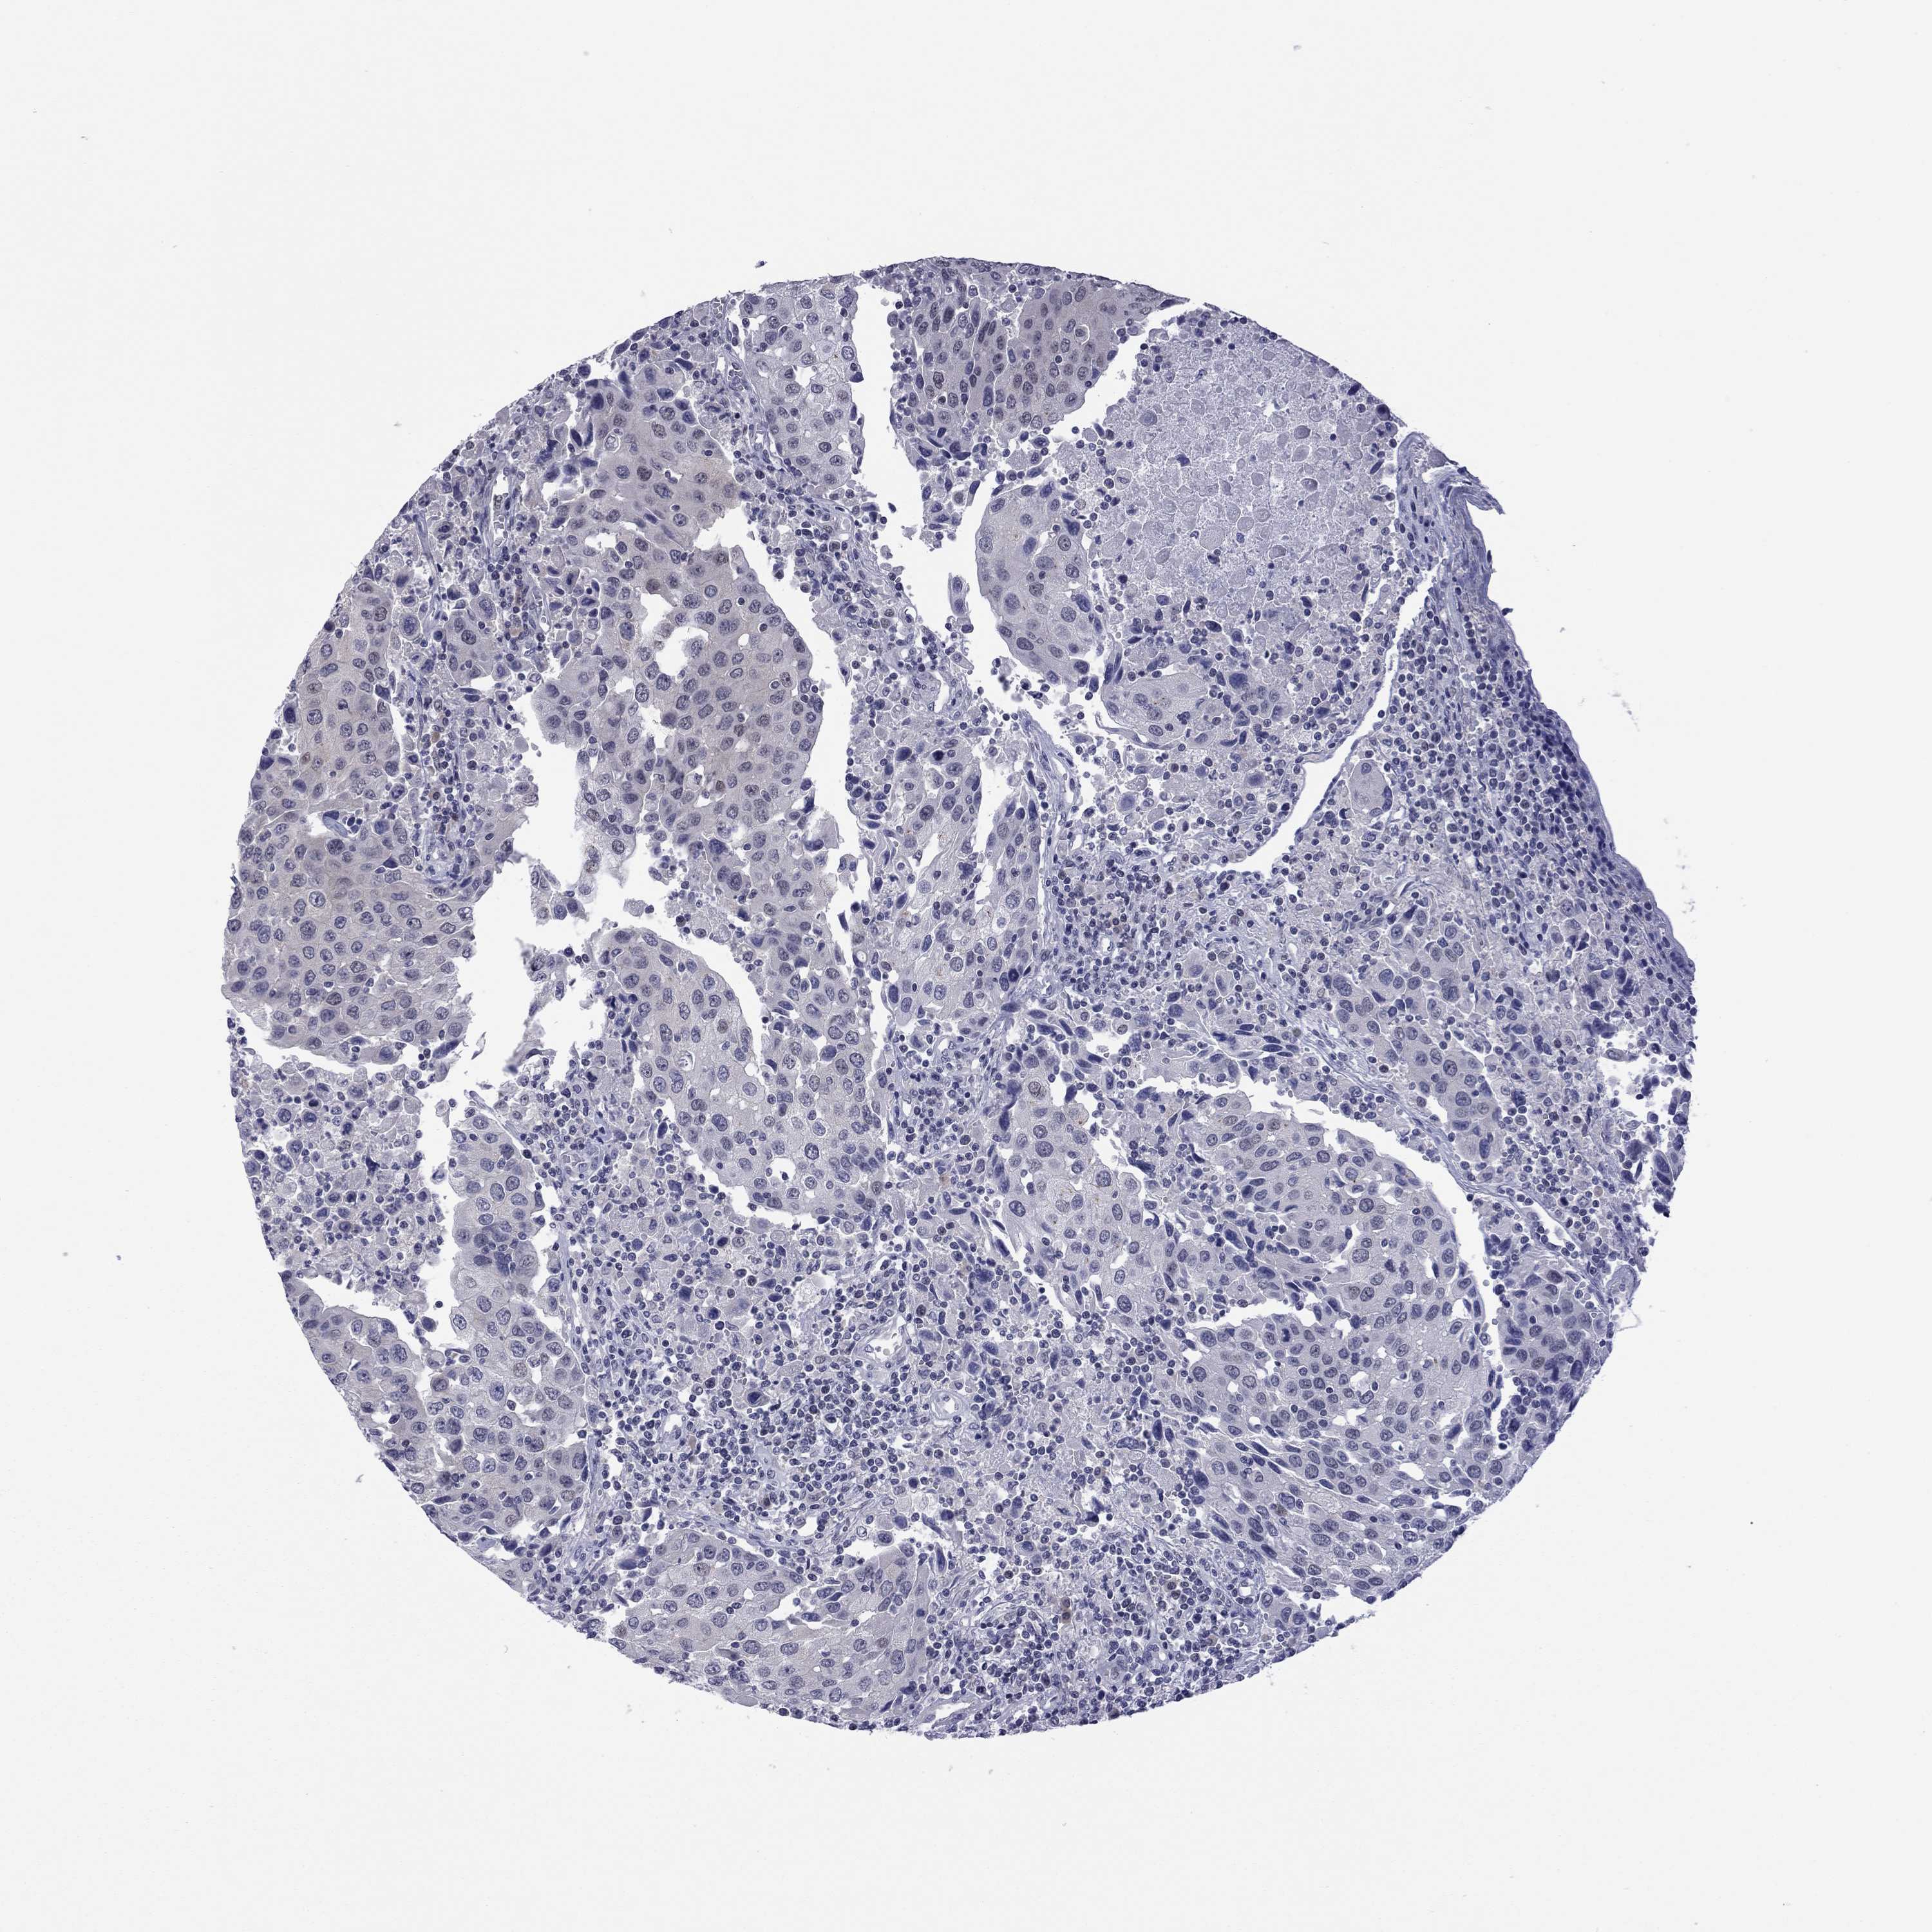

UROTHELIAL CANCER - Protein expressioni

A mouse-over function shows sample information and annotation data. Click on an image to view it in a full screen mode. Samples can be filtered based on level of antibody staining by selecting one or several of the following categories: high, medium, low and not detected. The assay and annotation is described here.

Note that samples used for immunohistochemistry by the Human Protein Atlas do not correspond to samples in the TCGA dataset.

Antibody stainingi

Antibody staining in the annotated cell types in the current human tissue is reported as not detected, low, medium, or high, based on conventional immunohistochemistry profiling in selected tissues. This score is based on the combination of the staining intensity and fraction of stained cells.

Each image is clickable and will lead to virtual microscopy that enables deeper exploration of all samples and also displays staining intensity scores, fraction scores and subcellular localization as well as patient and tissue information for each sample.

Antibody HPA077615

Staining

High

Medium

Low

Not detected

Intensity

Strong

Moderate

Weak

Negative

Quantity

>75%

75%-25%

<25%

None

Location

Nuclear

Cytoplasmic/membranous

Cytoplasmic/membranous,nuclear

Urothelial carcinoma, High grade

Urothelial carcinoma, Low grade